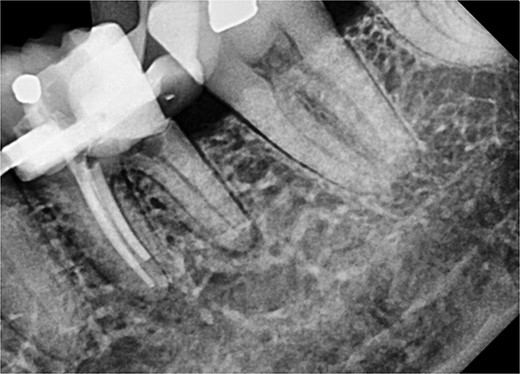

After removal of the existing restoration and caries, the cavity margin on the mesial side was noted to be 1 mm subgingival, with a mid-palatal margin extending to the root surface. Non-surgical root canal treatment was performed under local anesthesia and rubber dam isolation. Only the DB and DL canals were cleaned and shaped, and obturation was completed using ProTaper Gold gutta-percha with AH Plus sealer (Dentsply, Konstanz, Germany) (Fig. 8).

Periapical radiograph of tooth 36 with obturation on DB and DL canal. Sealer extrusion noted.